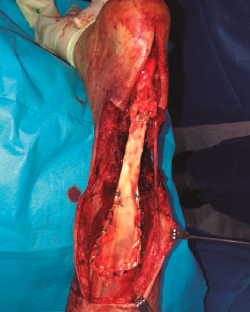

Figura 3. Fotografía intraoperatoria. Tras desbridamiento, se objetiva gap de unos 15 cm.

Se objetivó un defecto de 15 cm en el tendón calcáneo (Figura 3). Se aproximaron los bordes de la herida con seda quirúrgica y se realizó un vendaje compresivo.

Figura 5. Fotografía intraoperatoria. Muestra la sutura proximal de tipo Krackow y la anastomosis distal con muñón de tendón remanente.

La fijación se obtuvo a través de una sutura de tipo Krackow en la unión miotendinosa proximal y sutura término-terminal a nivel distal, al existir muñón distal suficiente (Figura 5). De forma simultánea, se realizó la cobertura cutánea con un colgajo fascio-cutáneo vascularizado del muslo del paciente (Figuras 6A, 6B y 6C).